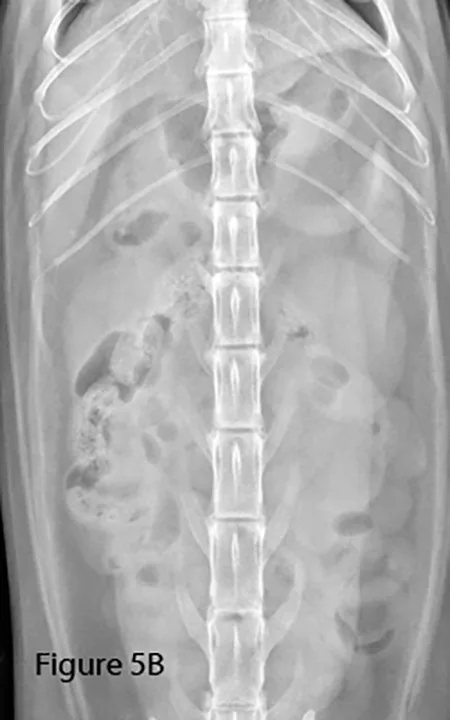

Lateral (Figure 5A) and ventrodorsal (Figure 5B) abdominal radiographs of a cat with string foreign body. Note the plicated (ie, ribbon candy) shape of small intestinal segments, bunched centrally. Pockets of triangular and odd-shaped abnormal intraluminal gas are present, common with linear foreign bodies.

To differentiate normal centralized small intestine from pathologic intestinal bunching, a plastic or wooden spoon may be used to place pressure on the lateral abdomen to disperse the intestinal segments. This cat demonstrated corrugation (ie, undulating serosal margins) of a segment of small intestine, seen in some cases of linear foreign body ingestion causing intestinal plication.